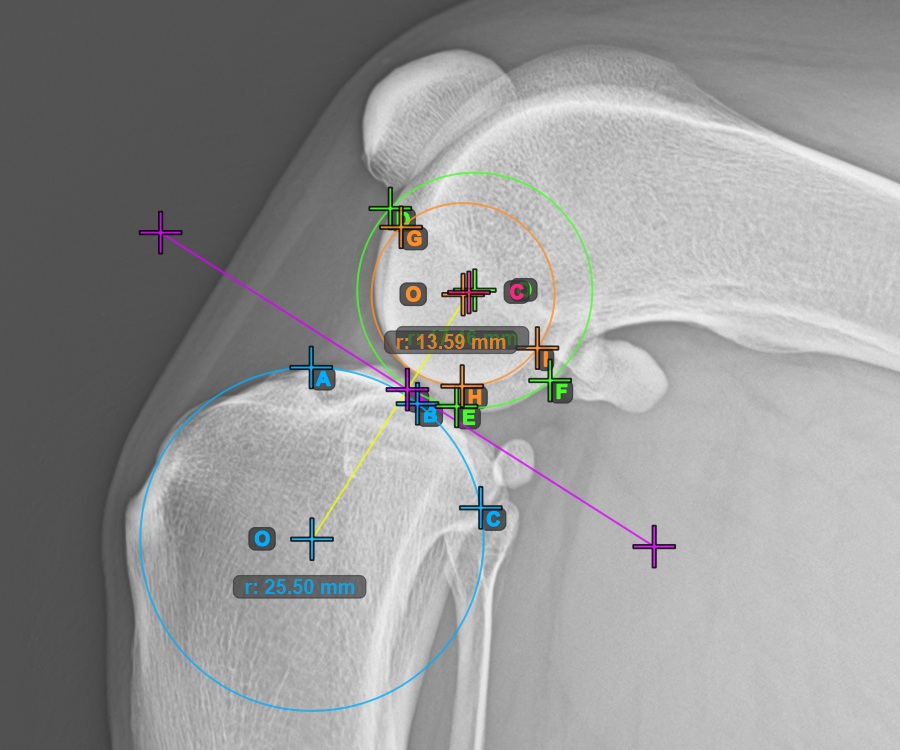

Jelölje meg a három pontot a tibia fő condylusán (Medialis Tibialis). A sorrendtől függetlenül ügyeljen arra, hogy megjelölje a legfelső pontot, a legalacsonyabb pontot és a Medialis Tibialis középpontját. A három pont alapján a rendszer automatikusan létrehoz egy kört.

A lenti kép a Condylus Medialis Tibialis-on elhelyezett három pont tipikus elhelyezkedését ábrázolja.